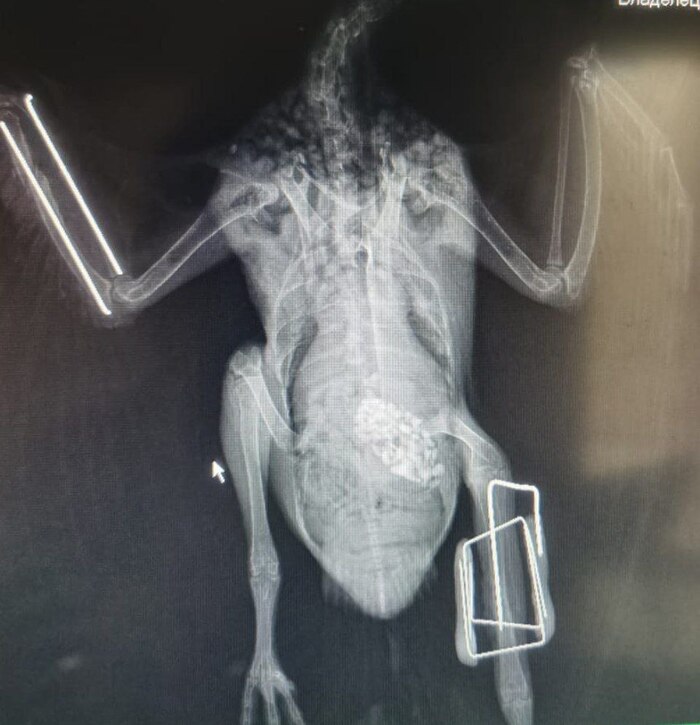

Сегодня расскажу немного про такой метод диагностики как рентген. В данном случае говорю только про своих, экзотических, пациентов.

Что это вообще такое - это метод лучевой диагностики, в котором используются рентгеновские лучи. При прохождении через ткани разной плотности они поглощают по-разному, поэтому мы и видим чёрно-белую картинку с 50 оттенками серого.

🩻 большой объём кишечника, который при повышенном газообразование может мешать визуализации органов на УЗИ

🩻 чаще всего делаем все тело, если нет жалобы на травмы конечностей

🩻 оцениваем легкие и сердечный силуэт параллельно с оценкой органов брюшной полости

🩻 хорошо видно костно-суставные патологии, это часто помогает найти причину хронической боли